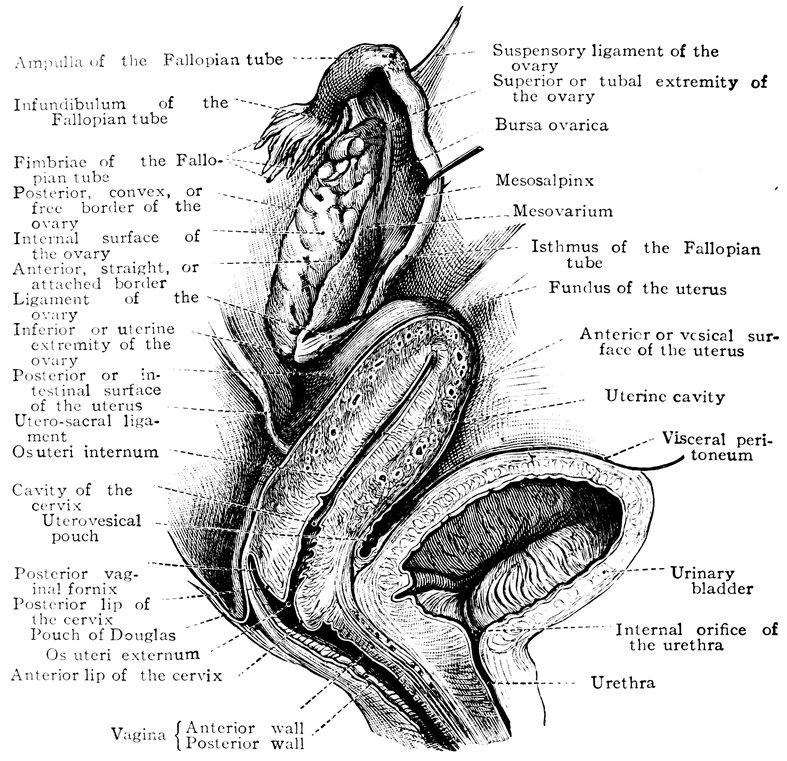

| 51. | Female internal genital organs in the fully developed state | 208 |